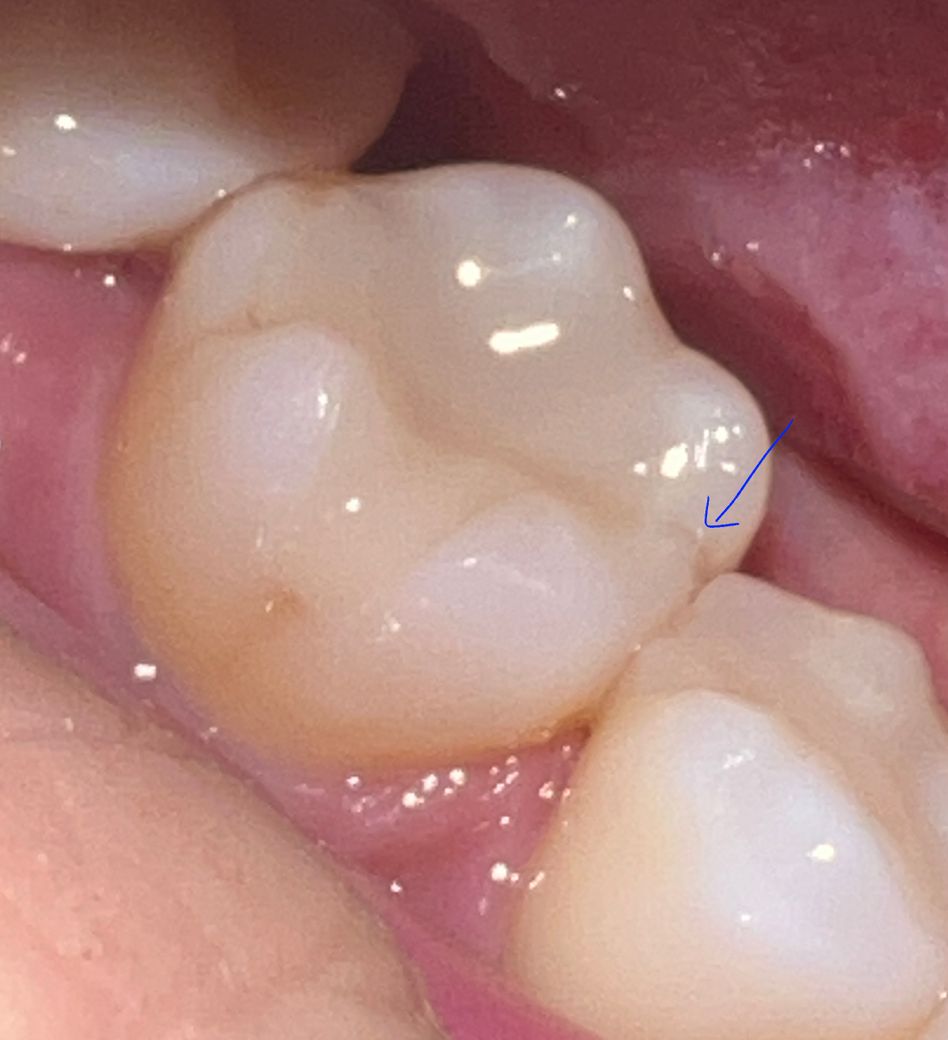

씹을 때 찌릿한 통증이 있어 큐레이로 검사해봤는데요.

큐레이상에선 붉은색 부분이 없는데 화살표 친 부분 금간거로 보이네요.

금간 거 아닌가요? 실금도 아닌 진한 금같아 보이는데요.

나중에 통증이 사라져도 크라운 안씌우고 그냥 인레이로 놔둬도 되나요?

계속 쓰다가 뿌리끝까지 금이 진행할수도 있지 않나요?